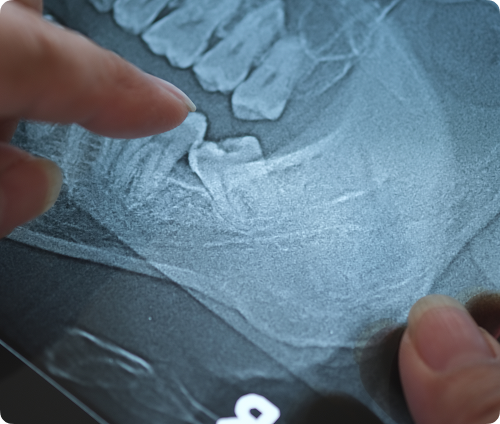

Même en l’absence de douleur, une évaluation clinique accompagnée d’une radiographie panoramique est utile pour déterminer si vos dents de sagesse risquent de poser problème. Dans plusieurs cas, une extraction préventive peut vous éviter des douleurs soudaines, des infections ou des déplacements dentaires à long terme.